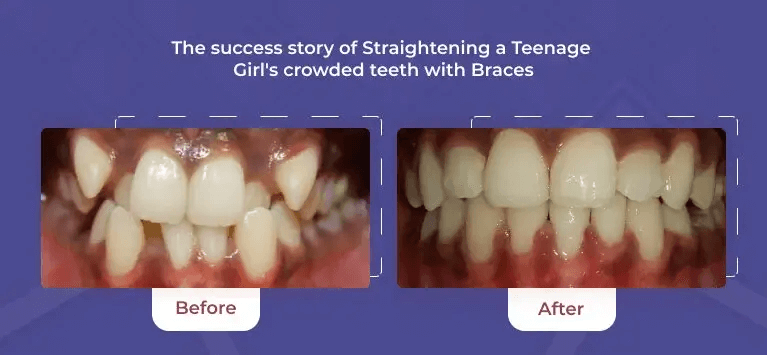

From routine cleanings and preventive care to advanced cosmetic and restorative dentistry, we offer a full range of dental services to keep your smile healthy and vibrant.

Creating Beautiful Smile

for All ages